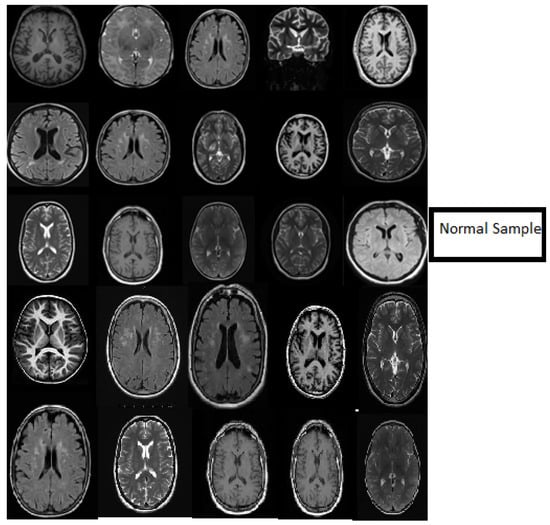

3. Datasets

- In classification, we applied a deep wavelet auto-encoder (DWAE) model. In this stage, the segmented MR brain image is resized by 256 × 256 × 1 dimension for faster processing. The objective of this stage is to predict the slices with tumor (abnormal MR brain images and the slices without tumor (normal MR brain images).